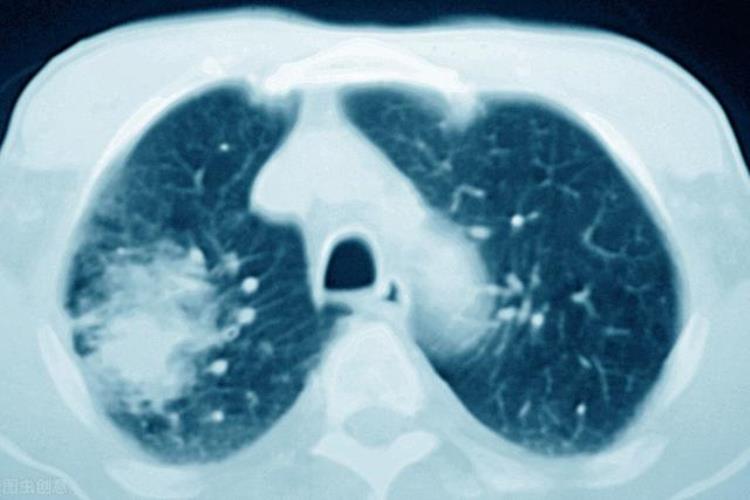

但是我发现有很多人及时发现恶性肿瘤,但是却没有及时发觉并治疗。我有一个患者,之前是因为糖尿病来诊,当时患者来时,反复咳嗽,并且觉得胸部疼痛,当时我通过四针合参,发现患者必有重病,于是建议患者到医院做一个肺部的检查,果不其然,检查报告下来后,被诊断为肺癌中期,因为体质差没有手术,单纯做了6个周期的化疗后,再次来诊。想以中医治疗。来诊时症见:神疲乏力、咳嗽、痰少色白质黏,无咳血,且伴有活动后气喘、食欲不振、睡眠质量差等症状,其舌质淡红、苔薄白,脉细,由于此患者年老体弱,加上平时劳累过度,在有糖尿病合并胃轻瘫,损伤了脾脏,以中医五行说解释就是土不生金,所以导致肺脾气虚,而且多疗程化疗后进一步损伤脾胃,导致正气亏虚严重,所以结合症状辨证为肺脾气虚,治以补肺健脾,止咳化痰为主。

肿瘤的治疗上存在有不同的观念、不同的认识,不同的理论体系,也就存在不同的方法和措施。很多医生和病人都存在误区,使病人走了不少弯路。例如,一位患者家属诉说,他的病人有咳嗽症状时,在郑大一附院检查CT,发现肺部阴影,但无法取到病理,即无法明确诊断。建议观察三个月,肿块大些了可以活检。结果三个月后复查,已经扩散了,医院无法治疗。从早期拖到晚期,不是这个专家水平低,而是不确诊就没法治疗,这是西医理论上的缺陷。